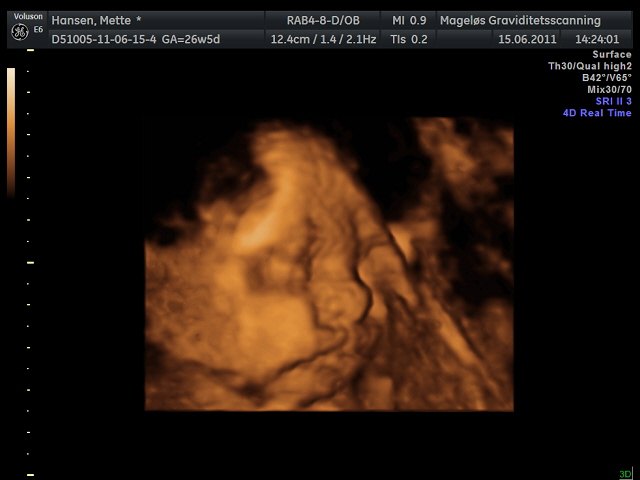

Mettefpigen

Hvor er de flotte de billeder i har lagt ind

Her er det min lille dreng  Han ville selvfølgelig ikk vise hele sit ansigt så har kun fået "noget" af det

Hihi men fik faktisk også et billede af hans dutti, så nu er vi 100% sikker på at det er en dreng  haha.. Så har vi det først billede til hans konfirmation

Vedhæftede fotos (klik for at se i fuld størrelse)